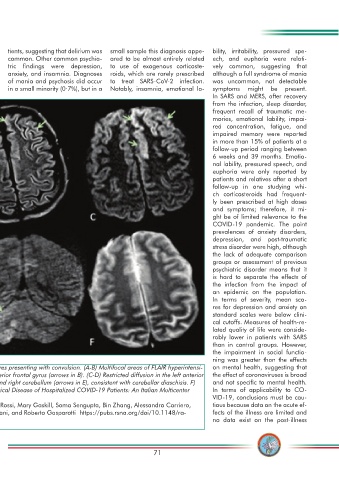

Image 2. Acute encephalopathy. A 60 year-old-man without history of seizures presenting with convulsion. (A-B) Multifocal areas of FLAIR hyperintensi- on mental health, suggesting that

ty in the right cerebellum (arrows in A), left anterior cingular cortex and superior frontal gyrus (arrows in B). (C-D) Restricted diffusion in the left anterior the effect of coronaviruses is broad

cingulate cortex, superior frontal and middle temporal gyrus (arrows in D) and right cerebellum (arrows in E), consistent with cerebellar diaschisis. F) and not specifi c to mental health.

No hemosiderin deposits in Gradient echo sequences. (Imaging in Neurological Disease of Hospitalized COVID-19 Patients: An Italian Multicenter In terms of applicability to CO-

Retrospective Observational Study VID-19, conclusions must be cau-

Abdelkader Mahammedi, Luca Saba, Achala Vagal, Michela Leali, Andrea Rossi, Mary Gaskill, Soma Sengupta, Bin Zhang, Alessandro Carriero, tious because data on the acute ef-

Suha Bachir, Paola Crivelli, Alessio Paschè, Enrico Premi, Alessandro Padovani, and Roberto Gasparotti https://pubs.rsna.org/doi/10.1148/ra- fects of the illness are limited and

diol.2020201933) no data exist on the post-illness